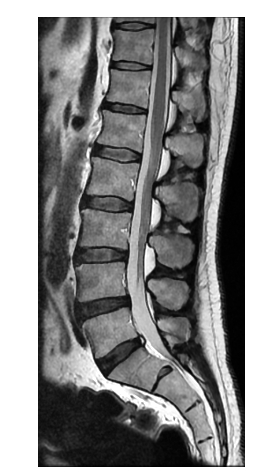

Scanner et IRM CLIGNANCOURT à Paris dans un centre spacieux et moderne

Nous sommes équipés de

deux scanners faible dose, de dernière génération, dotés d’intelligence artificielle permettant de dépister précocement les nodules suspects.